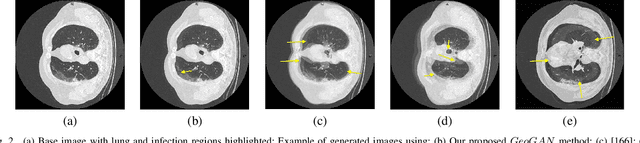

Abstract:While medical image segmentation is an important task for computer aided diagnosis, the high expertise requirement for pixelwise manual annotations makes it a challenging and time consuming task. Since conventional data augmentations do not fully represent the underlying distribution of the training set, the trained models have varying performance when tested on images captured from different sources. Most prior work on image synthesis for data augmentation ignore the interleaved geometric relationship between different anatomical labels. We propose improvements over previous GAN-based medical image synthesis methods by learning the relationship between different anatomical labels. We use a weakly supervised segmentation method to obtain pixel level semantic label map of images which is used learn the intrinsic relationship of geometry and shape across semantic labels. Latent space variable sampling results in diverse generated images from a base image and improves robustness. We use the synthetic images from our method to train networks for segmenting COVID-19 infected areas from lung CT images. The proposed method outperforms state-of-the-art segmentation methods on a public dataset. Ablation studies also demonstrate benefits of integrating geometry and diversity.